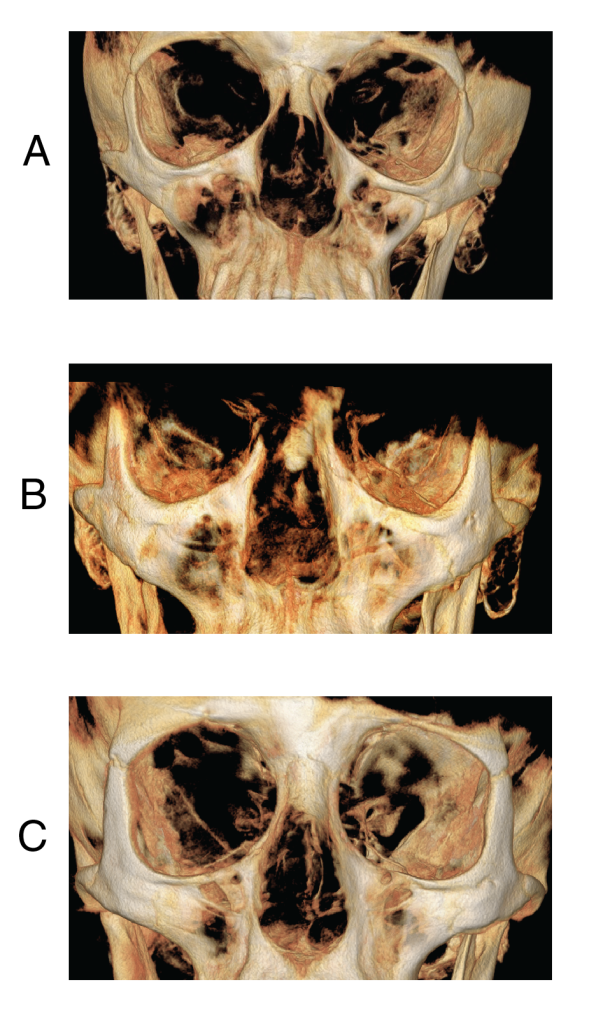

Figure 6: Condyle of a patient with Nemaline Myopathy. Radiographic images show the righ The right and left mandibular condyles of an NM patient (A), a matched open bite (B), and a matched control patient (C). The decrease in size, thinner cortical bone, less trabecular bone, and longer neck differentiate the NM patient from the matched patients.